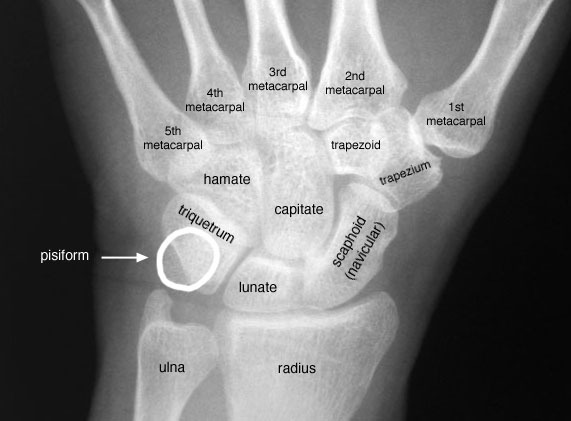

14. 8개의 수근골의 이름을 말하라.

모든 수근골을 기억하는데 유용한 잘 알려진 연상기호는 다음과 같다. (근위열의 요측에서 척측방향을 시작으로 원위열의 요측에서 척측방향 순)

"Some lovers try positions that they cannot handle."

scaphoid, lunate, triquetrum, pisiform, trapezium, trapezoid, capitate, hamate

주상골, 월상골, 삼각골, 두상골, 대능형골, 소능형골, 유두골, 유구골

trapezium과 trapezoid의 상대적 위치를 기억하는 한 가지 팁은 trapezium은 엄지(thumb)와 관련된다는 것이다.

△ Carpal bones (이미지 출처 : http://www.raddaily.com)